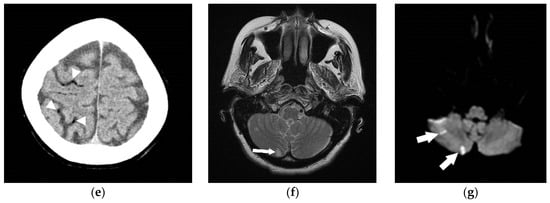

5. Air Embolism Management

5.2. Advanced Management

6. Hyperbaric Oxygen Therapy